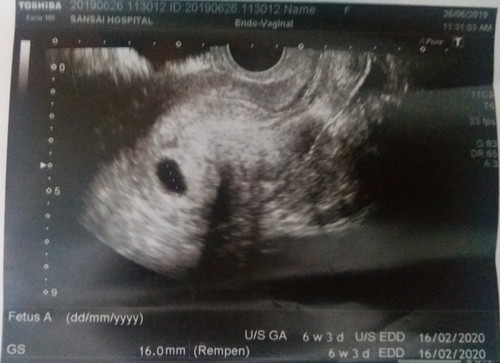

วันนี้ไปหาหมอไปฝากครรภ์ หมอขอตรวจซาวท้องแต่พอตรวจแล้วกลับไม่เจอถุงตั้งครรภ์ เลยให้ซาวช่องคลอดก็เจอถุงค่ะ อยู่ในมดลูก แต่ว่ายังไม่เจอตัวอ่อน ไม่ทราบว่าอายุครรภ์ยังน้อยอยู่รึป่าว 6w3d หมอให้คำตอบไม่ได้ 50/50 กลัวเป็นท้องลม แล้วเราเองมีเลือสีน้ำตาลออกมา2วันละค่ะ แบบมีนิดๆ กลัวว่าเป็นภาวะแท้งคุกคาม อีก3อาทิตย์หมอนัดซาวอีกที ขอให้อย่าเป็นอะไรเลยนะตัวเล็ก แม่รอหนูอยู่ เอาใจช่วยด้วยนะคะ